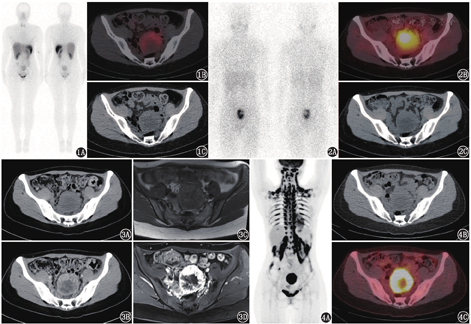

由于PPGL具有高表达生长抑素受体(somatostatin receptor, SSTR)并摄取NE的类似物间碘苄胍(meta-iodobenzylguanidine, MIBG)的特点,SSTR显像及131I-MIBG也是PPGL定位诊断的重要工具。SSTR显像诊断嗜铬细胞瘤的灵敏度约50%,但对肾上腺外的副神经节瘤的灵敏度达90%;而131I-MIBG显像诊断嗜铬细胞瘤的灵敏度为85%,诊断副神经节瘤的灵敏度为56%~75%[3],这其中的差别可能与嗜铬细胞瘤和肾上腺外副神经节瘤的功能不同、2种显像的生物分布和图像分辨率不同有关。本例患者行99Tcm-联肼尼克酰胺-酪氨酸3-奥曲肽(hydrazinonicotinamide-Tyr 3-octreotide, HYNIC-TOC)SSTR显像和131I-MIBG肾上腺髓质显像,均可见盆腔类圆形肿物,大小约6.3 cm×6.0 cm,显像剂摄取异常增高(图1,图2)。

本例定性诊断已明确——PPGL所致的继发性高血压,所以盆腔占位考虑PPGL可能性大。值得注意的是,部分非PPGL(或非神经内分泌肿瘤)也可能在SSTR显像或肾上腺髓质显像中表现为阳性,如胃肠道间质瘤、肾上腺皮质腺瘤、副脾、淋巴瘤、肝血管瘤、血管平滑肌脂肪瘤等在肾上腺髓质显像中可能表现为阳性,而乳腺癌、肾癌、肺癌、淋巴瘤、正常子宫或者子宫肌瘤等可在SSTR显像中出现高摄取[4]。为进一步明确病变诊断及其与周围组织、血管的关系,本例患者行增强CT和MRI,结果显示盆腔肿物明显不均匀强化(图3),符合PPGL的影像特点。

由于PPGL存在恶性潜能,并且1/4的患者可有多个解剖学起源(同时/异时存在多个病灶)[5],患者之后行18F-FDG PET/CT以评估病变良恶性及探测病灶数量,显像见盆腔病灶代谢异常增高,中心坏死,全身棕色脂肪代谢异常增高(图4),除此之外未发现其他病灶或转移灶。